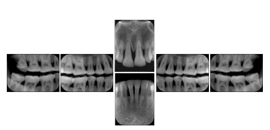

Table OO.1.1-1 shows structured display standard templates, where Viewset ID is based on the Japanese Society for Oral and Maxillofacial Radiology (JSOMR) classification provided by JIRA (Japan Medical Imaging and Radiological Systems Industries Association, www.jira-net.or.jp). Expected or typical teeth to be imaged location, region and designation codes are based on ISO 3950-2010, Dentistry - Designation system for teeth and areas of the oral cavity. For all the hanging protocols listed in OO.1.1-1, the value to use for Hanging Protocol Creator (0072,0008) is "JSOMR" and the value to use for Hanging Protocol Name (0072,0002) does not include "JSOMR" (e.g., "DL-S001A", not "JSOMR DL-S001A").

Table OO.1.1-1. Hanging Protocol Names for Dental Image Layout based on JSOMR classification